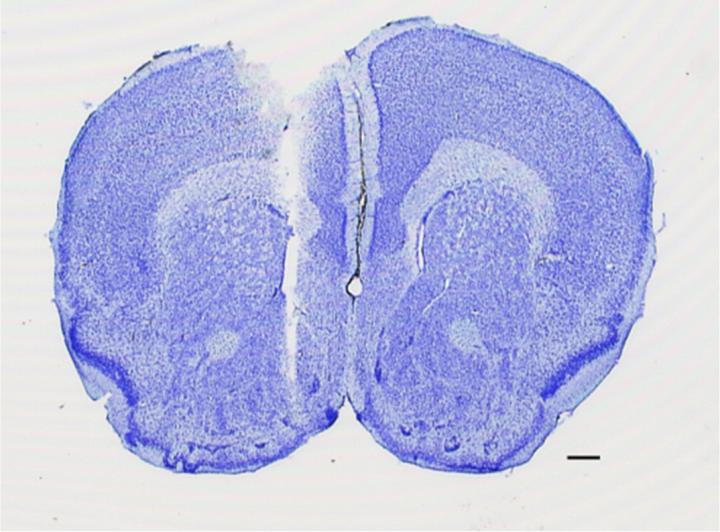

image: Coronal section from a representative experiment showing the microdialysis probe track ending within the medial nucleus accumbens shell. Scale bar, 5 mm. This material relates to a paper that appeared in the Jan. 11, 2017, issue of Science Advances, published by AAAS. The paper, by J. Bonaventura at National Institutes of Health in Baltimore, Md., and colleagues was titled, 'Key role of the dopamine D4 receptor in the modulation of corticostriatal glutamatergic neurotransmission.' view more

Credit: Bonaventura et al. <i>Sci. Adv.</i> 2017;3:e1601631